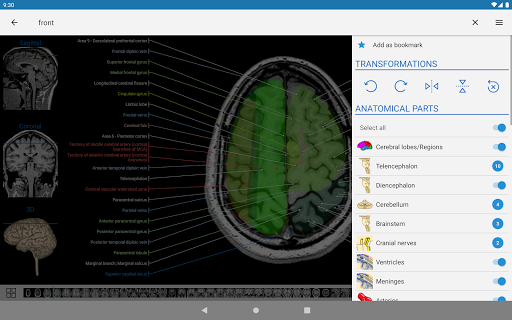

- Ketuk label untuk menampilkan struktur anatomi

- Pilih label anatomi berdasarkan kategori

- Anda sekarang dapat menyembunyikan struktur satu per satu (tombol baru di dalam tampilan deskripsi) dan menampilkannya lagi di menu sebelah kanan